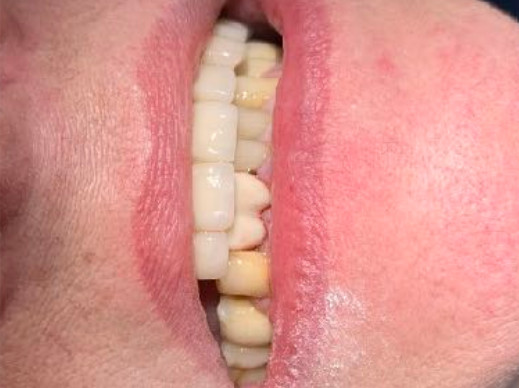

Non esistono bocche perfette, non ci sono organismi perfetti. Come medici/odontoiatri possiamo solo augurarci di incontrare bocche normali, anche se molto spesso non è così. E con il passare degli anni è più facile perdere salute e normalità piuttosto che trovarle. Consumiamo lo smalto, si abbassano le gengive, si approfondano le tasche, si cariano le corone.

A volte le consumiamo noi stessi col serramento, col bruxismo o perché le spazzoliamo con troppa energia. Perdiamo in seguito i denti per varie cause e così si abbassa il livello dell’osso. E alla fine perdiamo la vita stessa. Quante volte siamo stati o ci siamo sentiti perfetti? E allora.... Sorrido con amarezza ogni volta che sento colleghi cattedratici declamare il ritorno alla perfezione estetica e funzionale del sorriso dei loro pazienti. Noi no! Noi non crediamo a questa dichiarazioni false e ingannevoli. E non crediamo neppure che a questo siamo tenuti legalmente.